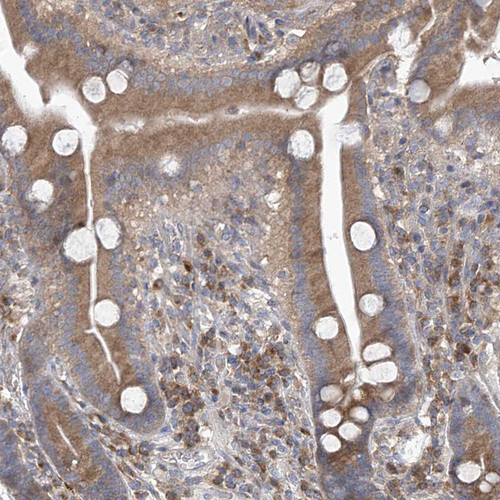

Immunohistochemical staining of human pancreas shows moderate cytoplasmic positivity in exocrine glandular cells.